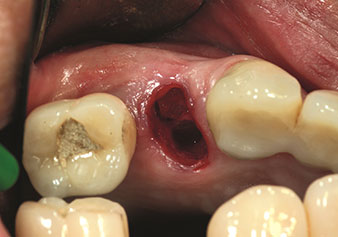

Endikasyon, dahili sinüs lifti

W&H ayrıca iç sinüs lifti için mükemmel bir çözüm sunar. Uygun aletlerle maksiller sinüs hazırlığından sonra

(Şekil 3), yeni uç Z35P (Şekil 4) ile membran hidrodinamik olarak kaldırılır. Aynı uç seti ayrıca Piezo cerrahisi yöntemiyle, artan çaplardaki implant yeri hazırlığı için de kullanılabilir [şekil 3 ve 4, Dr. Mario Kirste’nin (Frankfurt/Oder) onayı ile kullanılmıştır].

Uç I4P ile implant yeri hazırlama

Şekil 3: Uç I4P ile implant yeri hazırlama. Fotoğraf: © Dr. Mario Kirste (Frankfurt/Oder)